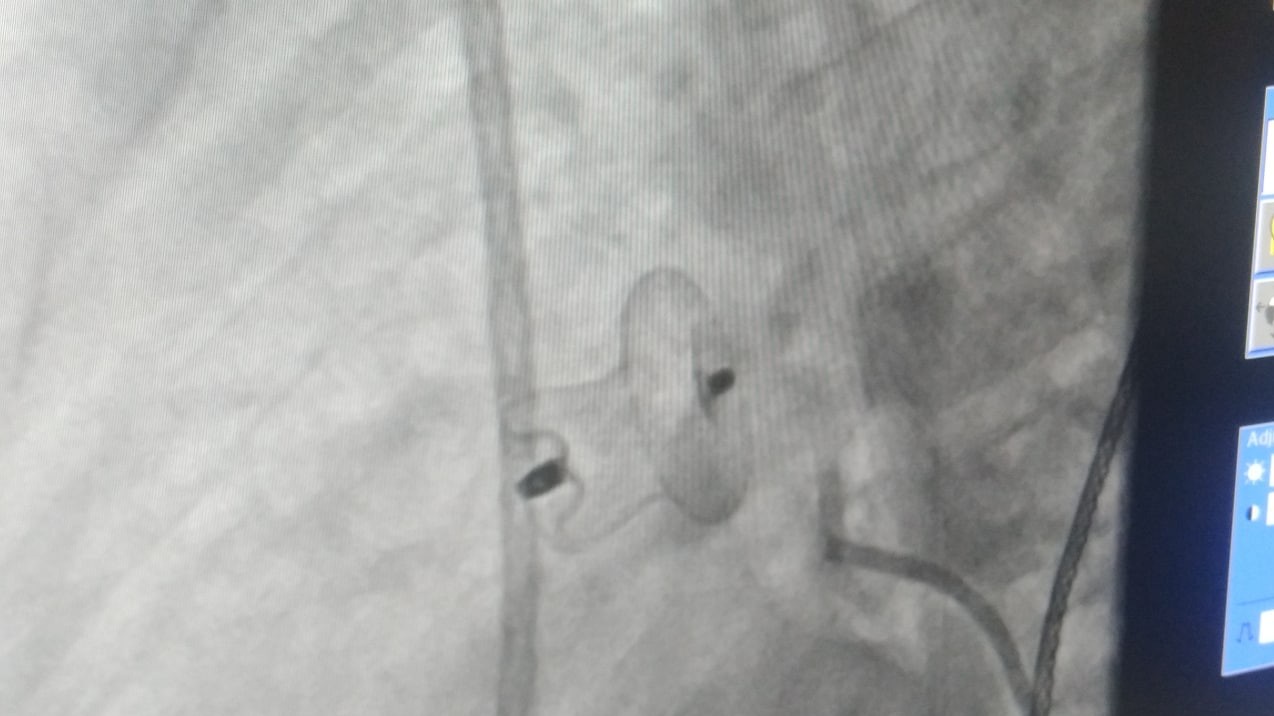

Бұл Сырдарияда осындай оталарды жүргізуге мүмкіндігін береді, – дейді эндоваскулярлық хирургия бөлімінің меңгерушісі Хуршид Хакимов. – Операциялық практиканың қолайлылығы сонда –  денеге ине тимейді, операция  аз уақытқа созылады. Сонымен қатар, операциядан кейінгі оңалту уақыты да қысқа. Ашық операцияда байқалатын қан кету, тігілген ақаулардың қайта ашылуы сияқты асқынулар байқалмайды.

Жоғары технологиялық эндоваскулярлық отаны Республикалық Балалар ұлттық медициналық орталығының жетекші мамандары сырдариялық эндоваскулярлық хирургтармен бірлесе отырып жасады. Нәтижесінде жүрек ақауы жойылды, деп хабарлайды Сырдария  облыстық денсаулық сақтау басқармасының баспасөз қызметі.